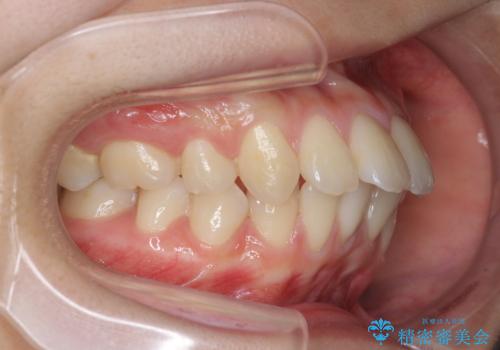

突き出た前歯の改善!マウスピースで再矯正

- 5年前にワイヤー矯正治療を終了したが、突き出たように見える前歯の仕上がりが気に入らず、再矯正治療を希望され来院されました。

マイクロインプラントを用いた遠心移動とIPRを行うことによる前歯の突出感の改善をマウスピース矯正治療で計画します。

突出していた前歯の角度が大きく改善し、審美的な仕上がりに満足いただくことができました。